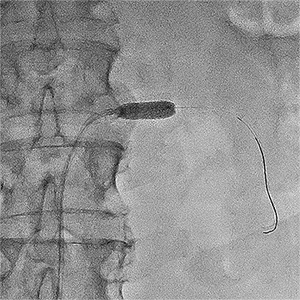

Ангіограми до та після стентування:

стеноз лівої ниркової артерії    балон, роздутий в зоні стенозу    відновлення отвору артерії

Субтотальний стеноз лівої

ниркової артерії

Балон-катетер зі стентом,

роздутий в зоні стенозу

Отвір артерії повністю відновлено